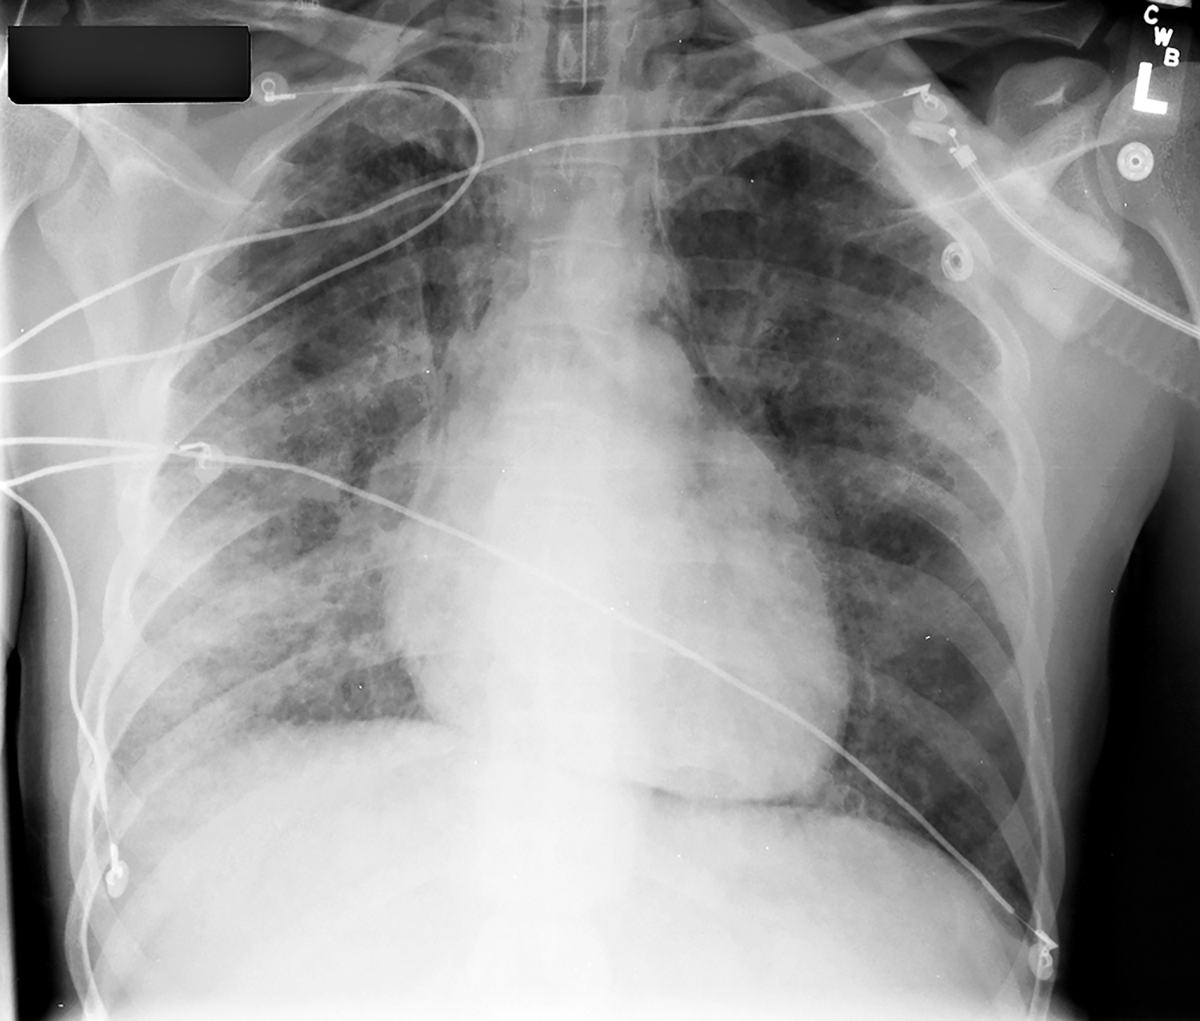

intermediate case for other abnormal air